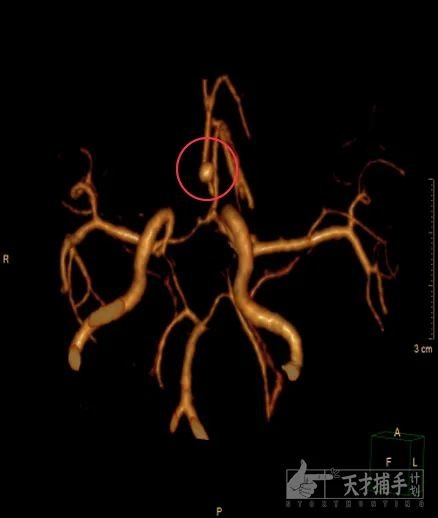

陈主任沉默半响,找我要来了上午给珊珊做的增强CT(头部扫描)。

我打开电脑,滑动鼠标一帧一帧地控制片子。

“停,就这里!”陈主任让我停下来。

在珊珊受伤的组织那里,他看了一个可疑的影子,但无论怎么观察,还是无法判断它是什么。

陈主任要我给CT室打电话,做血管重建,用更多更精细的角度去观察这个阴影,必须想办法得出结论。

他看到有个可疑的突起,陈主任认定那就是炸弹埋藏的地方——

那是人体血液的核心管道,大脑前动脉!

“这应该是一个动脉瘤。”

正好CT室那边把图像上传了上来——他们说,陈主任没判断错,这就是一个动脉瘤。

增强血管像,可以看到那个罪魁祸首,它就是那个动脉瘤

更不好的消息是,这可能是一百例动脉瘤里仅会出现一个,致死致残率高达百分之五十的创伤性动脉瘤。

趁着消毒铺巾的功夫,我也去看了一眼。一个莹亮的芒果尖样的小包,从血管壁上凸起。